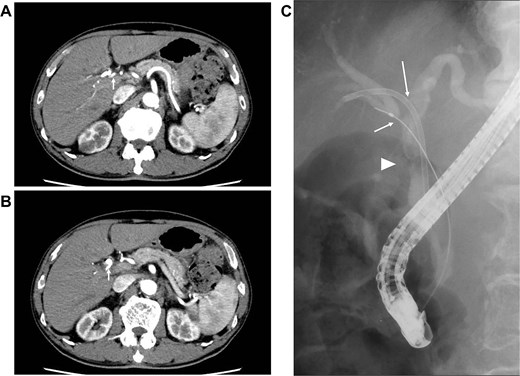

Seven cycles of GCD immunochemotherapy were performed (gemcitabine 1000 mg/m2 on days 1 and 8; cisplatin 25 mg/m2 on days 1 and 8; and durvalumab 1500 mg on day 1 in a 21-day cycle). During this period, GC administration on day 8 was discontinued in three of the seven cycles owing to granulocytopenia or decreased renal function, which was judged as Grade 2 according to Common Terminology Criteria for Adverse Events v5.0 [3]; however, durvalumab could be administered in all cycles. Dynamic CT performed after the seven cycles of GCD immunochemotherapy revealed significant tumor shrinkage and the disappearance of RHA invasion (Fig. 2A). Moreover, lymph node metastasis had disappeared (Fig. 2B). Post-chemotherapy ERC demonstrated markedly improved CHD narrowing; however, bile duct stenosis was noted at the confluence of the right anterior and posterior bile ducts (Fig. 2C). From these findings, efficacy assessment demonstrated a partial response, rendering the tumor resectable.

Images after seven cycles of GCD immunochemotherapy (A and B) dynamic CT demonstrating the tumor has shrunk and that the infiltration into the RHA has disappeared (arrow). The enlarged lymph node has also disappeared. (C) ERC revealing a significantly improved CHD stricture (arrow head); however, the stricture at the confluence of the anterior and posterior branches persists (arrow).